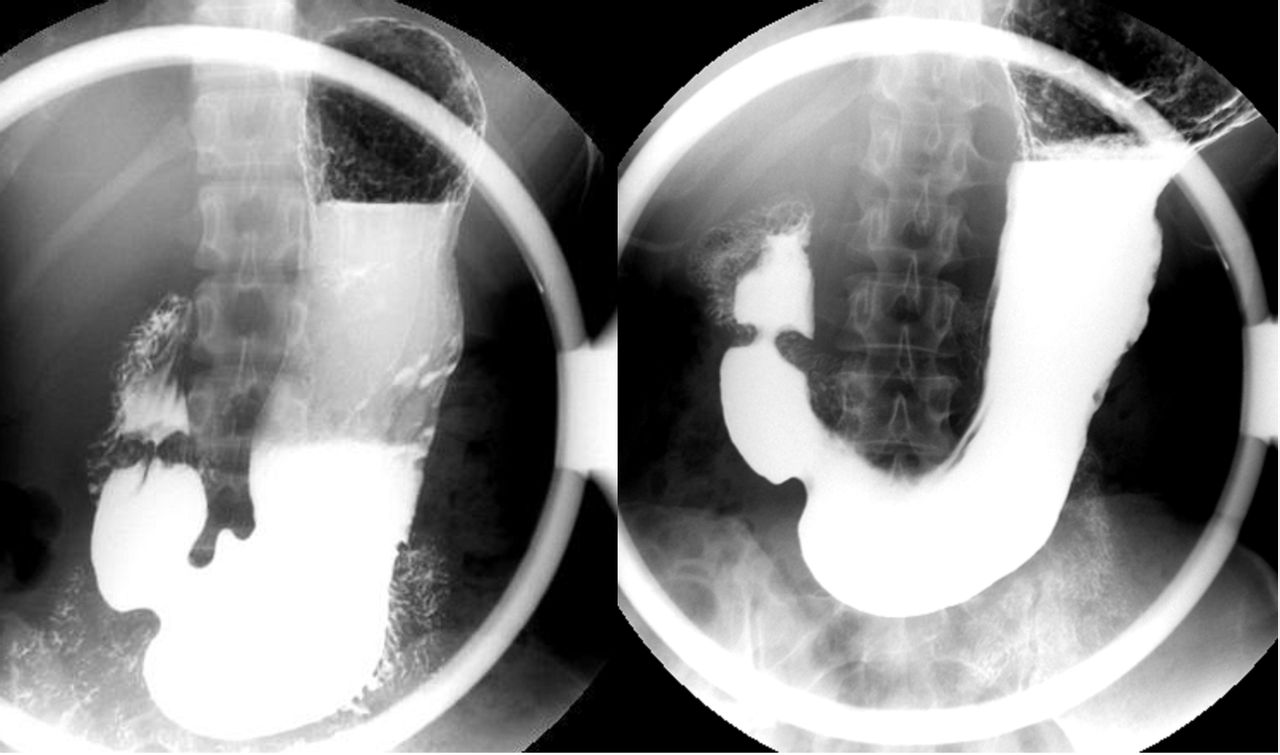

那些年胃肠镜还不像现在这么普及,80多岁的老人做肠镜的也比较少,因此医生选择了钡餐检查,全消化道钡餐。就是喝进去钡剂,钡剂在肠道里不透X线,如果有溃疡,钡剂就会充填溃疡面,影像会凸出来,医学上叫做“龛影”;如果长东西,那一块儿的钡剂影像就会缺损,这样就能发现疾病了。

全消化道钡餐,说起来是“全消化道”,但实际上只是检查到回盲部,就是回肠和盲肠交界的地方,长阑尾的地方。到了盲肠之后,才是大肠,包括结肠、直肠。所以,全消化道钡餐实际上只是检查了从食管、胃到小肠,没有检查到大肠。

钡剂检查大肠怎么做?钡灌肠,用灌肠的方法把钡剂灌到大肠里检查。